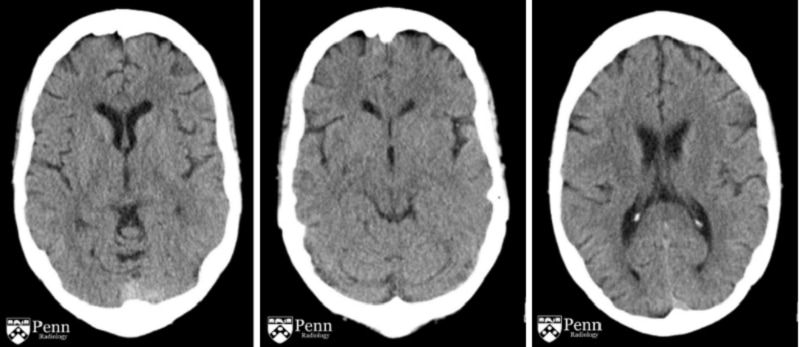

Bệnh Wernicke

Bệnh não Wernicke (WKS) là một hội chứng rối loạn hệ thần kinh (não bộ) do thiếu vitamin B1 gây nên. Thực chất, các nhà khoa học cho rằng bệnh não Wernicke và hội chứng mất trí nhớ Korsakoff là hai giai đoạn khác nhau của cùng một hội chứng rối loạn trí nhớ. Wernicke là giai đoạn đầu của hội chứng và Korsakoff là giai đoạn mãn tính, nếu kéo dài sẽ nguy hiểm điến tính mạng (có thể dẫn đến tử vong).

Bệnh nhân mắc phải hội chứng Wernicke - Korsakoff thường có các triệu chứng như:

Nhìn đôi (song thị) hoặc có hiện tượng ảo giác

Mất khả năng vận động, khó khăn trong việc đi lại

Hạn chế giao tiếp của người bệnh

Thiếu tỉnh táo, dễ mất tập trung, suy giảm trí nhớ

Tuy WKS có ảnh hưởng xấu đến cơ thể, sức khỏe cũng như tâm lý của con người, tuy nhiên vẫn có thể chữa trị nếu bệnh nhân chịu hợp tác bằng các biện pháp như:

Cai rượu (nếu có)

Truyền thiamin bằng đường ống hoặc tĩnh mạch ở bàn tay

Đảm bảo chế độ ăn không thiếu vitamin B1